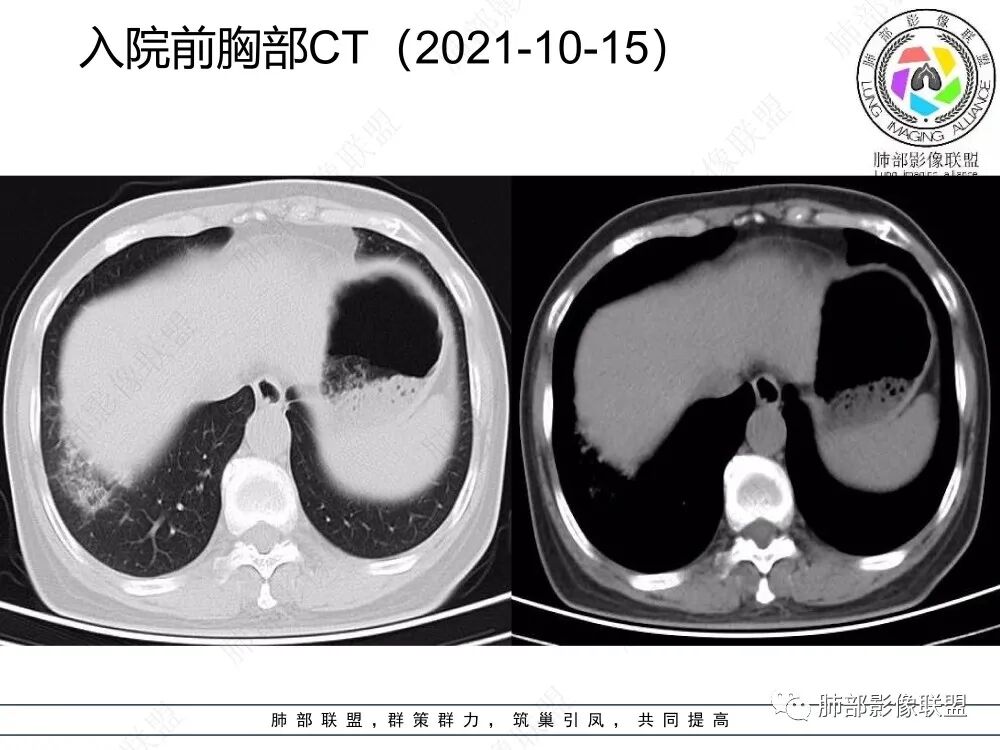

1、老年女性,急性病史,以咳嗽咳痰伴发热就诊,白细胞不高,肺炎支原体阴性,C反应蛋白增高,提示存在感染性病变。

2、CT表现为两肺下叶结节影、斑片影、磨玻璃影,沿支气管血管束分布,部分支气管壁显示增厚。粗略一看部分病灶内似可见“细网格影”,但是仔细观察,可发现此“细网格影”不同于我们常见的“细网格影”,尤其是右肺下叶病灶,可以观察到病灶内部的网格上有高密度结节感或颗粒感,部分层面见“反晕征”,且反晕的边缘亦可观察到结节感。未见胸腔积液。

本例病变以两肺下叶为主,非结核好发部位,通常会想到感染性病变,右肺下叶病灶高密度结节感、反晕征,较为符合继发性肺结核(间质浸润为主),但双肺散落的相对柔和淡薄小片影给诊断带来困惑。